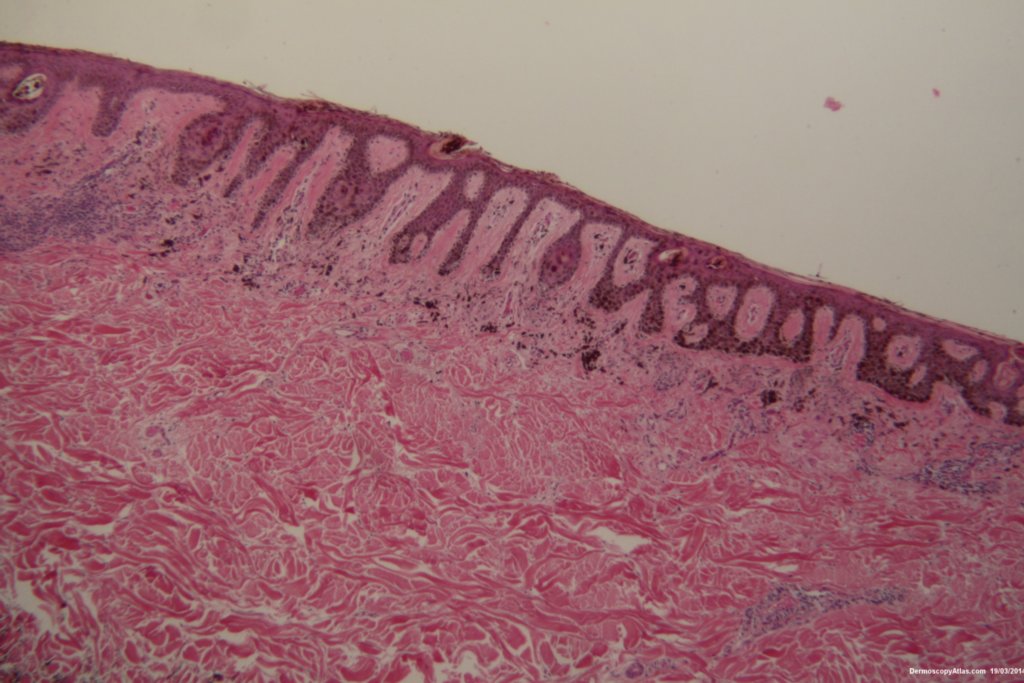

Diagnosis: Dysplastic Junctional Lentiginous Nevus

An elderly male asked about the pigmented lesion on his lower back. The dermatoscopy showed internal lines and dark clods with a central dark structureless area. Histology showed a dysplastic junctional lentiginous nevus.